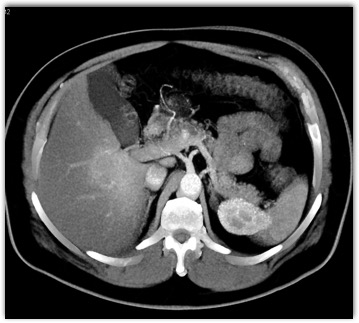

The best diagnosis in this case is?

NASH

focal liver sparing

hepatoma

cirrhosis